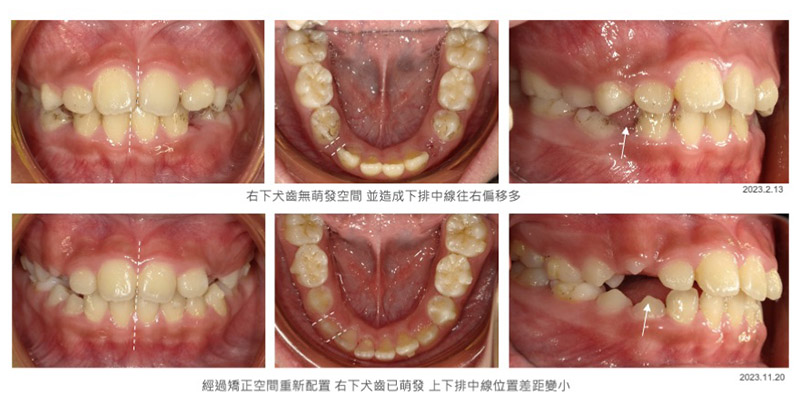

直到今年我九歲的女兒因為右邊下排的乳犬齒比較早脫落,使缺牙區前後的牙齒往缺牙空間傾倒,因此導致成人犬齒萌發空間變小及下中線往右飄移,甚至下巴也連帶向右偏移。這個時候我突然能體會帶孩子來諮詢的父母心情,原來看在父母眼裡,就算一點點凌亂或歪斜也會很想把握孩子能提早矯治的機會!(我終於又懂了父母心??!! 難怪爸爸媽媽會很擔心)因此我開始思考要不要幫女兒進行矯正,如果要矯正,又該用什麼方式進行?

從今年二月女兒開始進行矯正,治療目標以空間調整至右下犬齒有萌發空間為主,整齊度倒是其次,因此小豆豆(attachment)的黏著數量不多,以減低清潔的困難度,經過矯正九個月後,有這些改變:

- 右下犬齒的萌發空間已經挪出並且順利萌出

- 牙弓形狀達到標準U型

- 下中線及下巴偏移改善

兒童隱適美矯正前後牙齒變化